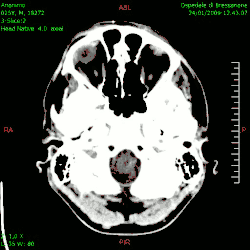

En las imágenes de TC y RM se muestra como una lesión heterogénea, de contorno irregular, que capta contraste en anillo y con un área central necrótica.

Diagnóstico por imagen y glioblastoma

La TC muestra una lesión de morfología irregular, predominantemente hipodensa y fuertemente dishomogénea, debido a la presencia de grandes áreas necróticas de más clara hipodensidad y de áreas sólidas hiperdensas. Estas últimas son la expresión de un rápido crecimiento y por lo tanto de una elevada malignidad. Son frecuentes las zonas hemorrágicas, que van desde pequeños focos a grandes áreas hemáticas que pueden cubrir toda la lesión. Es característica la morfología en "mariposa" si el tumor se asienta en ambos hemisferios a través del cuerpo calloso.

Tras la aplicación de contraste aparecen gruesos anillos alrededor de las áreas necróticas. En la RM, la parte sólida aparece hipointensa en T1 e hiperintensa en T2 con zonas de señal más elevada en las partes de mayor celularidad. Las áreas necróticas, hiperintensas en T2, pueden presentarse hipo-, iso- o hiperintensas en T1 en función del contenido proteico o de productos de la degradación de la hemoglobina. El realce tras el contraste suele ser intenso e irregular en la periferia del tumor e identifica sobre todo la componente celular "proliferativa" de la neoplasia. Son comunes las áreas puntiformes y serpiginosas de ausencia de señal de flujo, asociadas a la presencia de una neovascularización rica. Estos vasos de neoformación patológica carecen de barrera hematoencefálica, lo que explica tanto la abundante impregnación como el edema vasogénico perilesional (véase la sección anterior), debido al paso de líquido al medio extracelular.[72][73]